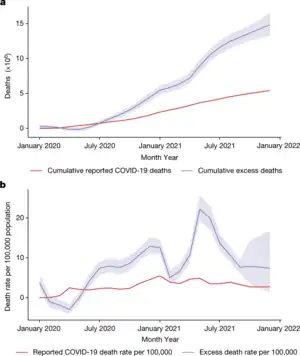

As of 10 March 2023, more than 6.88 million[5] deaths had been attributed to COVID-19. The first confirmed death was in Wuhan on 9 January 2020.[62] These numbers vary by region and over time, influenced by testing volume, healthcare system quality, treatment options, government response,[63] time since the initial outbreak, and population characteristics, such as age, sex, and overall health.[64]

Multiple measures are used to quantify mortality.[65] Official death counts typically include people who died after testing positive. Such counts exclude deaths without a test.[66] Conversely, deaths of people who died from underlying conditions following a positive test may be included.[67] Countries such as Belgium include deaths from suspected cases, including those without a test, thereby increasing counts.[68]

Official death counts have been claimed to underreport the actual death toll, because excess mortality (the number of deaths in a period compared to a long-term average) data show an increase in deaths that is not explained by COVID-19 deaths alone.[69] Using such data, estimates of the true number of deaths from COVID-19 worldwide have included a range from 18.2 to 33.5 million (≈27.4 million) by 18 November 2023 by The Economist,[4][69] as well as over 18.5 million by 1 April 2023 by the Institute for Health Metrics and Evaluation[70] and ≈18.2 million (earlier) deaths between 1 January 2020, and 31 December 2021, by a comprehensive international study.[71] Such deaths include deaths due to healthcare capacity constraints and priorities, as well as reluctance to seek care (to avoid possible infection).[72] Further research may help distinguish the proportions directly caused by COVID-19 from those caused by indirect consequences of the pandemic.[71]

In May 2022, the WHO estimated the number of excess deaths by the end of 2021 to be 14.9 million compared to 5.4 million reported COVID-19 deaths, with the majority of the unreported 9.5 million deaths believed to be direct deaths due the virus, rather than indirect deaths. Some deaths were because people with other conditions could not access medical services.[73][74]

A December 2022 WHO study estimated excess deaths from the pandemic during 2020 and 2021, again concluding ≈14.8 million excess early deaths occurred, reaffirming and detailing their prior calculations from May as well as updating them, addressing criticisms. These numbers do not include measures like years of potential life lost and may make the pandemic 2021's leading cause of death.[75][76][61]

Semi-log plot of weekly deaths due to COVID-19 in the world and top six current countries (mean with cases)

Semi-log plot of weekly deaths due to COVID-19 in the world and top six current countries (mean with cases).webp.png.webp) Excess deaths relative to expected deaths (The patterns indicate the quality of the all-cause mortality data that were available for each respective country.)[61]

Excess deaths relative to expected deaths (The patterns indicate the quality of the all-cause mortality data that were available for each respective country.)[61].webp.png.webp) Excess deaths relative to expected deaths (global and WHO region)[61]

Excess deaths relative to expected deaths (global and WHO region)[61] The 25 countries with the highest total estimated COVID-19 pandemic excess deaths between January 2020 and December 2021[61]

The 25 countries with the highest total estimated COVID-19 pandemic excess deaths between January 2020 and December 2021[61].webp.png.webp) The 25 countries with the highest mean P-scores (excess deaths relative to expected deaths)[61]

The 25 countries with the highest mean P-scores (excess deaths relative to expected deaths)[61]